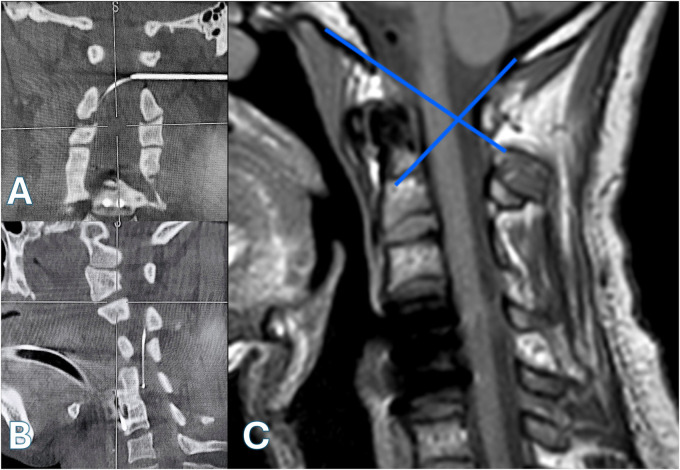

Spasticity is a neurological disorder that disrupts the regulation of muscle tone following an injury to the central nervous system, such as spinal cord injury. Baclofen is the most effective medication for treating spasticity and can be delivered via a pump connected to an intrathecal catheter. The catheter is typically inserted via a lumbar punction and advanced up to the level corresponding to the disturbing spasticity. But this may not be possible, especially when cervical level is involved. We present the case of a patient with severe spasticity after a traumatic cervical spinal cord injury who successfully underwent a lateral C1-2 puncture for placement of a retrograde catheter to the C4 level, after an unsuccessful attempt at catheter placement via a lumbar puncture. The patient experienced a significant reduction in spasticity with no reported worsening during the 8 months follow-up period. The catheter placement via a lateral C1-2 puncture guided by innovative imagery with 3D reconstruction, may serve as an effective and safe alternative to deliver baclofen at the cervical level. Relevance of cervical ITB is discussed and issues involved are considered. The mechanism of action of ITB at cervical level, which is far from fully clarified, is crucial to reach the best clinical outcome and avoid si de effects and complications. Few clinical cases were published; hence the importance to present this case.